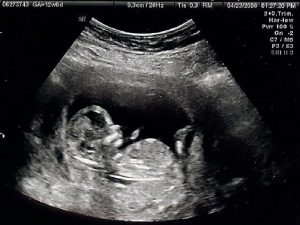

1. 超聲檢查

超聲心動圖是在超聲或超聲波的幫助下獲得心臟醫學圖像的過程。它允許醫生通過將心臟暴露于超聲波并檢測在撞擊心臟壁或心室后反射回來的波來獲得心臟的移動或實時圖像。超聲心動圖的過程是無痛和安全的。